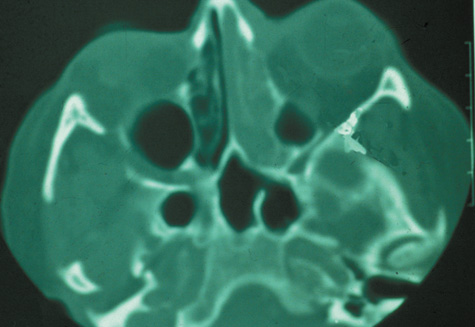

Computed tomographic findings in patients with both forms of the disease demonstrate areas that are almost metallic in density. These foci of irregularly calcified bone on CT may be pathognomonic (Fig. 22). On MRI, these areas appeared bright on T1-weighted imaging and have decreased signal on T2-weighted images, which may be related to the presence of ferromagnetic materials such as iron and manganese within the fungal concretions.115

Fig. 22. Aspergillosis. Computed tomography shows areas of extreme density of the ethmoidal bones.